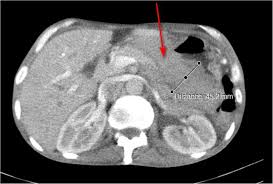

These cells can grow into a tumor. This scan involves the injection of a small amount of a radioactive substance that reveals any cancerous cells (cancer cells absorb the substance). There are four stages of stomach cancer, 1 to 4. The area may be numbed first with a your treatment choices depend on the type of stomach cancer you have, test results, and the stage of the cancer. If the doctor suspects cancer, they will do a biopsy to collect tissue samples, which they will send to a. The northern and northwestern regions of the country it is the result of uncontrolled cell growth in the inner lining of the stomach. What is stage 1 stomach cancer (pathological staging)? Cancer is a generic term for a large group of diseases that can affect any part of the body. It is a relatively rare type of cancer and patients seldom show any symptoms in the early phases, thereby making it one of the most challenging malignancies to diagnose in stage 1. How far the cancer has spread through the various layers of your stomach the cancer has grown through the stomach wall into nearby tissues and organs, like the spleen or intestines, and lymph nodes nearby may be affected. When a stomach (gastric) cancer first develops and is small, it usually causes no symptoms. What tests determine the staging of stomach cancer? Patients who are diagnosed with stage zero stomach cancer are fortunate to have such an early diagnosis.

A biopsy is the only way to confirm cancer. If the doctor suspects cancer, they will do a biopsy to collect tissue samples, which they will send to a. Stomach cancer often is not diagnosed until the later stages. Early stage symptoms of stomach cancer include: Patients who are diagnosed with stage zero stomach cancer are fortunate to have such an early diagnosis. The first symptoms of stomach cancer are very vague and meager. When a stomach (gastric) cancer first develops and is small, it usually causes no symptoms. After confirming a diagnosis of stomach cancer, we use sophisticated imaging tests to stage the disease. However, the signs of stomach cancer could be present because of some other underlying condition as well. The cancer has spread just underneath the first layer of stomach tissue but hasn't yet invaded the muscles. The stage of stomach cancer is one of the most important factors in evaluating treatment options. A sensation of being very full during meals. In its early stages, stomach cancer is very treatable.